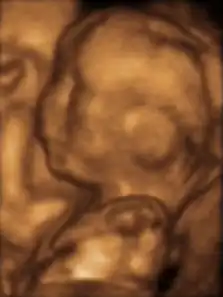

Fetus at 20 weeks

Fetal assessments

Obstetric ultrasonography is routinely used for dating the gestational age of a pregnancy from the size of the fetus, determine the number of fetuses and placentae, evaluate for an ectopic pregnancy and first trimester bleeding, the most accurate dating being in first trimester before the growth of the foetus has been significantly influenced by other factors.[22] Ultrasound is also used for detecting congenital anomalies (or other foetal anomalies) and determining the biophysical profiles (BPP), which are generally easier to detect in the second trimester when the foetal structures are larger and more developed.[23]

The safety of frequent ultrasound scanning has not been confirmed. Despite this, increasing numbers of women are choosing to have additional scans for no medical purpose, such as gender scans, 3D and 4D scans.[27] A normal gestation would reveal a gestational sac, yolk sac, and fetal pole.[28]